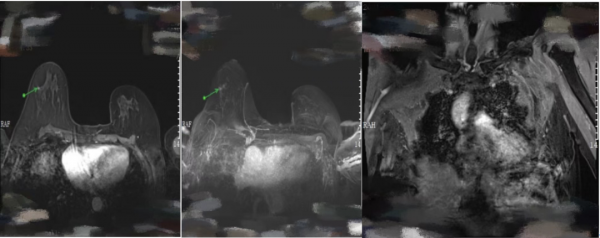

2021年06月08日,乳腺磁共振成像(MRI)檢查提示:右乳外上象限見段樣非腫塊強化,未達乳頭,T2WI-Tirm呈不均勻高訊號,DWI呈高訊號,ADC較低值約1.415*10-3mm2/s,增強掃描內部簇環狀強化,時間訊號強度曲線呈平臺型;雙乳另見大小約0.3cm強化結節,邊界清;右側腋窩淋巴結增大,大小約1.0cm,左側腋窩未見明顯腫大淋巴結;雙側胸大肌未見明顯異常,雙側面板、皮下、乳頭及乳暈未見明顯異常訊號(圖2)。

2021年08月26日,2個週期TCbHPy新輔助治療後,乳腺MRI複查提示:與基線(圖2)相比,右乳外上象限見簇狀分佈強化結節,較大約0.5cm,範圍較基線明顯縮小;雙乳見一大小約0.3cm強化結節,邊界清;雙側腋窩未見明顯腫大淋巴結;雙側胸大肌未見明顯異常;雙側面板、皮下、乳頭及乳暈未見明顯異常訊號(圖4)。